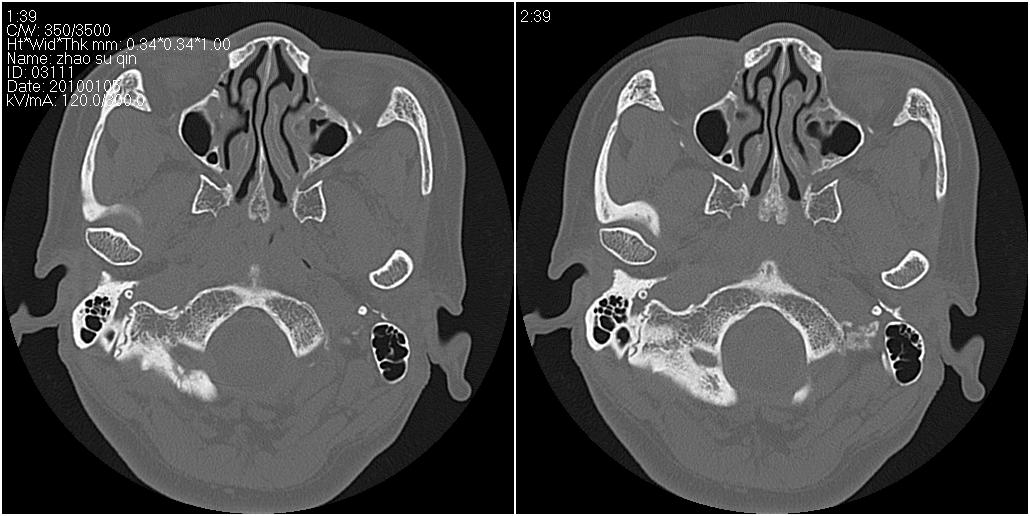

标题: CT24015:一个头部外伤患者进行鉴定,除了左侧筛板骨折,哪 [打印本页]

标题: CT24015:一个头部外伤患者进行鉴定,除了左侧筛板骨折,哪

看了几遍,其余未见明显骨折征。

左眶下裂部好像有骨折 似有小碎骨片

1)左侧筛板骨折。2)双侧筛窦炎症(或积血)。

其余未见明显骨折征。